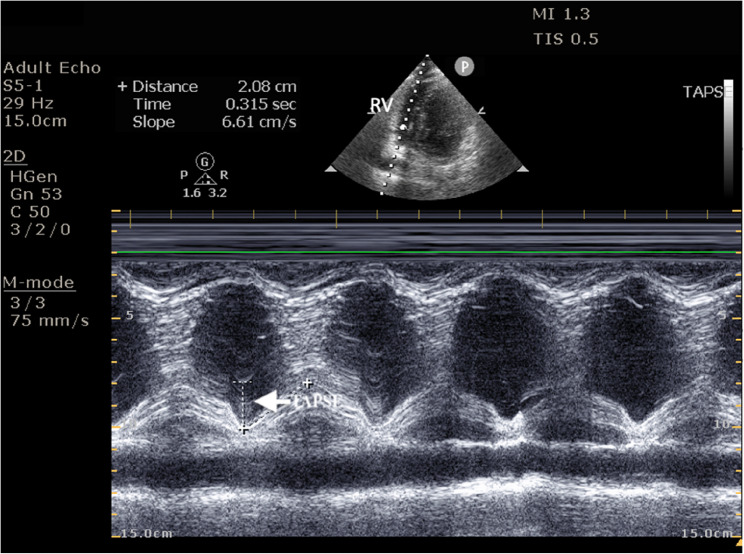

Background: Post-intubation hypotension (PIh) is a frequent complication following drug-assisted intubation, leading to increased morbidity, mortality, and healthcare costs. Pre-intubation hemodynamic factors, acid-base imbalances, and existing comorbidities, particularly right ventricular dysfunction, which is a lesser-known variable, have emerged as a critical predictor of PIh. Since RV systolic motion is predominantly longitudinal, TAPSE on POCUS provides a time-sensitive surrogate of RV function for high risk patients in the Emergency department.

Methods: Aim: The study aimed to list hemodynamic predictors and their correlation with easily executable POCUS and point-of-care echocardiography variables, which can impact emergency decision-making and optimal management in PIh. This prospective observational study was conducted in the Department of Emergency Medicine at Kasturba Medical College, Manipal, Manipal Academy of Higher Education, Manipal, Karnataka, India. 172 patients aged ≥ 18 years undergoing drug-assisted intubation were observed. Baseline demographics, clinical parameters, hemodynamic indices, and pre-intubation echocardiographic values (TAPSE, EPSS) were recorded. Shock index and modified shock index were calculated. Point-of-care ultrasound (POCUS) assessed left and right ventricular function. PIh within 30 min was defined as SBP [Formula: see text] 90mmHg, ≥ 20% fall in SBP, MAP < 65mmHg or new vasopressor initiation. Associations were tested with logistic regression. TAPSE discrimination was obtained with ROC analysis and Youden's Index.

Results: Of the 172 patients, 71 (41.2%) developed PIh. Patients with obstructive lung disease (59.3%, p = 0.039) and sepsis (66.7%) were significantly more likely to experience PIh. TAPSE values were significantly lower in those with PIh (17.66 ± 2.45 mm vs. 18.54 ± 2.15 mm, p = 0.014). The multivariate logistic regression revealed TAPSE as an independent predictor of PIh (OR = 0.81, 95% CI = 0.69-0.95, p = 0.009). ROC analysis of TAPSE showed moderate predictive power (AUC 0.584, 95% CI 0.497-0.672), with a cut-off of 17.6 mm (sensitivity 85.1% and specificity 29.6%).

Conclusion: TAPSE measured pre-intubation emerged as a reliable predictor of post-intubation hypotension. Incorporating a rapid assessment of right ventricular function using POCUS into the airway management algorithm provides valuable insights in identifying patients at higher risk of PIh.